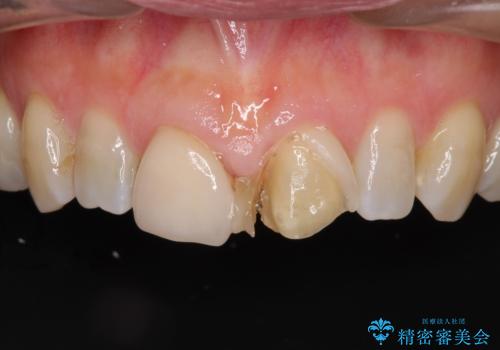

- 前歯のすきっぱを主訴にご来院された患者様です。他院でつめものやラミネートべニア(前歯の表面のみセラミックを貼り付ける)を行っていましたが、頻繁に外れることに悩まれており、クラウン(歯全体をセラミックがつつむ)をご希望されました。また、奥歯に大きな虫歯があり、歯が割れていたため、奥歯の治療も併せて行いました。

今回はまず欠けた場所を修復して見た目を回復させたのち、ラミネートべニアの仮歯をつくり、しばらく使用して考えて頂きました。メリットやデメリットを説明した結果、外れにくいセラミッククラウンをご選択頂きました。

咬み合わせや元のご自身の歯の色に特徴があったため、セラミッククラウンを修正したり、隣の歯を金属を外して白いつめものに変えたりして経過観察を長めに行いました。

ラミネートべニアのメリットは歯を削る量が少ない、デメリットは形態に限界がある、色の再現性に限界がある、外れやすい、境目から虫歯になりやすい等があります。

セラミッククラウンのメリットは比較的に色や形態が自由、外れにくい、デメリットは歯を削る量が多いのでしみる場合は根管治療が必要になる等があります。

今回は幸い、しみる症状がなかったため根管治療は行いませんでした。